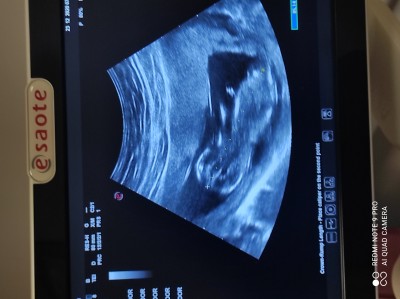

12+4  devlet hastanesi daha görünmez dedi de sizce özele gitsem belli olur mu?

Gebelik haftası 12+6